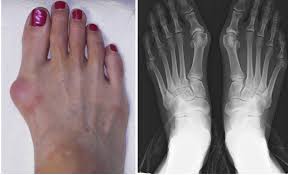

Čukljevi – sami po sebi su naslage soli. Njihovom formiranju doprinose: gripa, angina, giht, loš metabolizam, pogriješna ishrana, reumatske infekcije i dugo nošenje neudobne obuće.

Čukljevi na nogama su prava „noćna mora“ za ljude: veoma je teško pronaći odgovarajuću obuću, žuljaju, smetaju, bole i pored svega toga – daju vrlo ružan izgled noge.